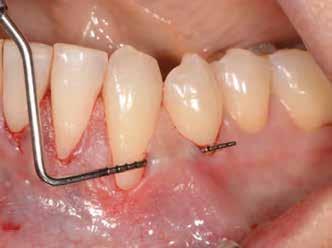

Az 50 éves nőpáciens az alsó és felső állcsont területén egyaránt panaszt (fájdalom, ráharapási érzékenység) okozó, harmadfokban mozgatható fogak miatt jelentkezett rendelőnkben. Az általános anamnézisben említést érdemlő betegség, műtét nem szerepelt. Az elvégzett klinikai és radiológiai vizsgálatok (1–2. ábra) alapján fogai reménytelen parodontális státusúnak bizonyultak, hosszú távon sem megtartásuk, sem protetikai célú felhasználásuk nem volt lehetséges. A parodontális prognózis a fogak eltávolításának abszolút indikációját jelentette. Ezáltal mindkét állcsontban teljes foghiány kialakulásával kellett számolnunk. A protetikai szemléletű, „visszafelé” tervezés elveit követtük a hosszú távú funkcionális, esztétikai siker és szöveti stabilitás elérése érdekében: mindkét állcsontban overdenture típusú fogpótlás készítése mellett döntöttünk. A megfelelő implant-protetikai rehabilitáció alapja az implantátumok megfelelő pozicionálása. A korábbi parodontális kórfolyamat következtében a processus alveolarisokat érintő eredendő csontdeficittel kellett számolnunk, amelyet tovább súlyosbíthatott volna a hagyományos extrakciós technikát követő involúciós atrófia. Ezért a páciens kivizsgálása és megfelelő előkészítése után a fog eltávolításával egy időben PRF

Sticky Tooth segítségével kivitelezett alveolus prezerváció mellett döntöttünk, a megfelelő csontos és mukogingivális gyógyulás minőségi és mennyiségi elősegítése érdekében. A PRF készítmény mennyiségét, minőségét, kezelhetőségét és hatékonyságát jelentősen befolyásolják a páciens laborértékei, ezért kezelési protokollunk szerint a műtétet megelőzően minden esetben laborvizsgálatot végzünk (hemoglobin: 134 g/liter, hematokrit: 0,43, fehérvérsejt: 6,6 G/liter, CRP: 13,60 mg/liter, vércukor: 6,2 mmol/liter, összkoleszterin: 7,00 mmol/liter, triglicerid: 1,08 mmol/liter, HDL koleszterin 2,57 mmol/liter, LDL koleszterin 1,12 mmol/liter), D3 vitamin: 117,5 nmol/liter).

A fogak eltávolítása és az alveoláris csont megőrzésének és regenerációjának segítése céljából elvégzett augmentáció altatásban történt. Óvatos, atraumatikus extrakciót követően eltávolítottuk a parodontális és periapikális gyulladásos folyamatok eredményeként jelen lévő sarjszövetet. A bukkális csontfal hiánya és a tervezett vertikális augmentáció miatt indokolt membrántechnika megfelelő kivitelezése céljából a felső állcsonton mukoperioszteális lebenyt képeztünk (3–4. ábra). Az alveolus prezervációt Sticky Tooth, PRF és titánerősítésű teflon (PTFE-Ti) membránok segítségével végeztük el, a J. Choukroun által megadott vérvételi és centrifugálási protokoll (28) elveinek betartásával: kizárólag Process for PRF Duo Quattro System eszközöket, centrifugát, vérvételi egységet és csöveket, a membránok előállításához PRF Boxot használtunk. Az A-PRF és S-PRF csöveket a PomPac eljárásnak megfelelően 4 Celsius-fokra előhűtöttük. Az eltávolított fogak makroszkópos tisztítását és darabolását nagy fordulattal (300 000 RPM) fogászati turbinába helyezett gyémántfúróval végeztük, majd Tooth Transformer™ berendezéssel, annak gyári reagens rendszerével kezelt őrleményt nyertünk. A Sticky Tooth készítmény előállítása a PRF készítmény és az őrlemény